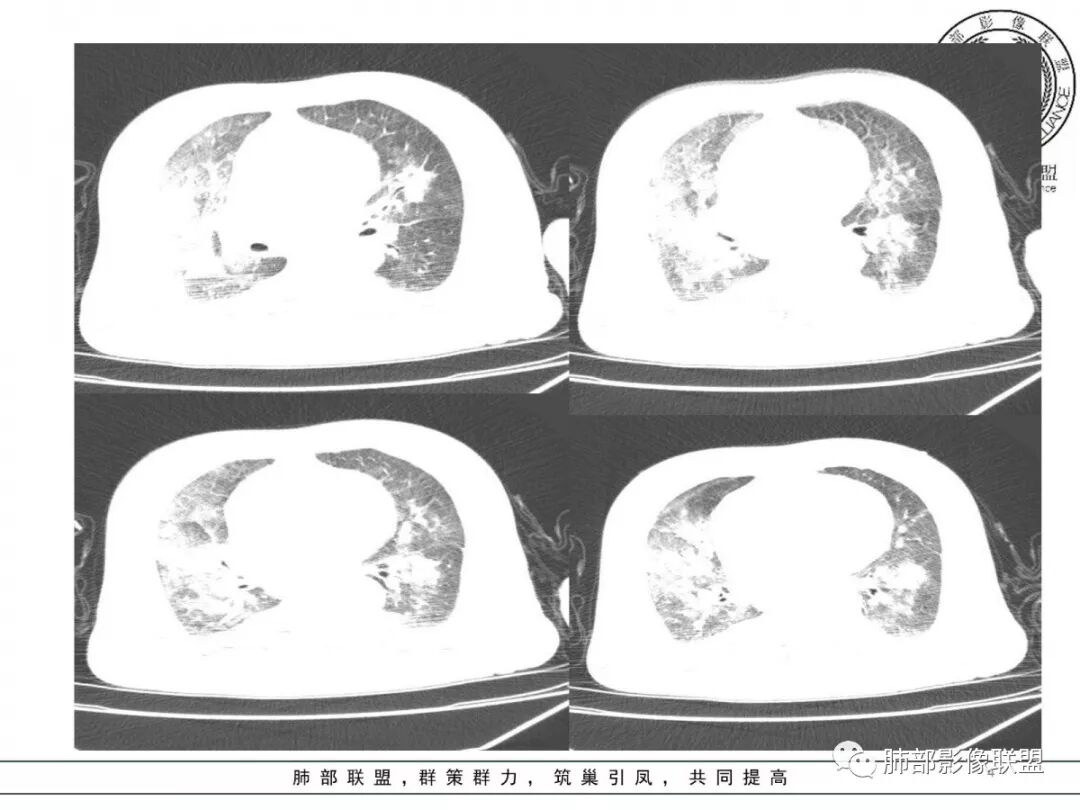

有结果,以下是治疗6天后

综合考虑:心源性肺水肿

这个不能叫有结果,印象诊断。什么原因造成的肺水肿呢?没有病毒的结果,没有病原学,结果诱因的结果,整个过程来看,应该是爆发性的心衰,但是心肌酶的结果也没有。

因为其他的因素造成的,不会这么快可逆。心梗六天,夹层或者其他的造成的心功能衰竭,六天可逆不了,唯一可逆的就是爆发性心肌炎可逆很快的。因为心肌会修复,酶的指标下来他就能好转。

熊老师是考虑病毒继发的心衰,从病史看,还是支持;影像上:肺水肿是明确的;如果病毒性肺炎影像上重叠

这个肺水肿,它的所谓变化快,是进展可以快,但是他不一定消退可以快。只有这个人抢救过来才消的快,但是还有更多的情况下抢救不过来,是越来越重的。所以影像不应该单纯考虑吸收很快,不一定的。

病毒导致的心衰,不是病毒导致的肺炎,两个虽然都会水肿,但过程不一样,影像表现也不一样。

一个急性心衰,虽然没给酶的指标,但我觉得应该有心肌酶一过性的爬峰,后来又回落。别的,这么大面积的心梗,心功能不会这么快好转的,血运重建之后也会有损伤的。

但是没有明显的纤维化变化,病毒说实话,不敢说;如果吸收过程中有OP样改变,病毒就依据更充分

对,这个病史都不到一周。病毒性肺炎从病史的角度来讲是不符合的。

肺水肿肯定有;就是有无病毒性肺炎,也就是病因是啥的问题

所以从前面没有发热就基本不会有病毒性肺炎。从来后面六天的吸收来看,就完全排除了病毒性肺炎。病毒肺炎吸收至少一个月以上。

独居老人,肺部病变吸收符合肺水肿诊断,考虑原有心脏基础病变,已经有心功不全可能,本次感冒(病毒感染)是诱发加剧的原因之一,至于考虑病毒性心肌炎诊断,值得商榷。大面积心梗、病毒性心肌炎,导致肺水肿或心原性性休克,过去称泵衰竭,泵衰竭,临床上没有怎么好转快。这个病例,应该没有病毒性肺炎。